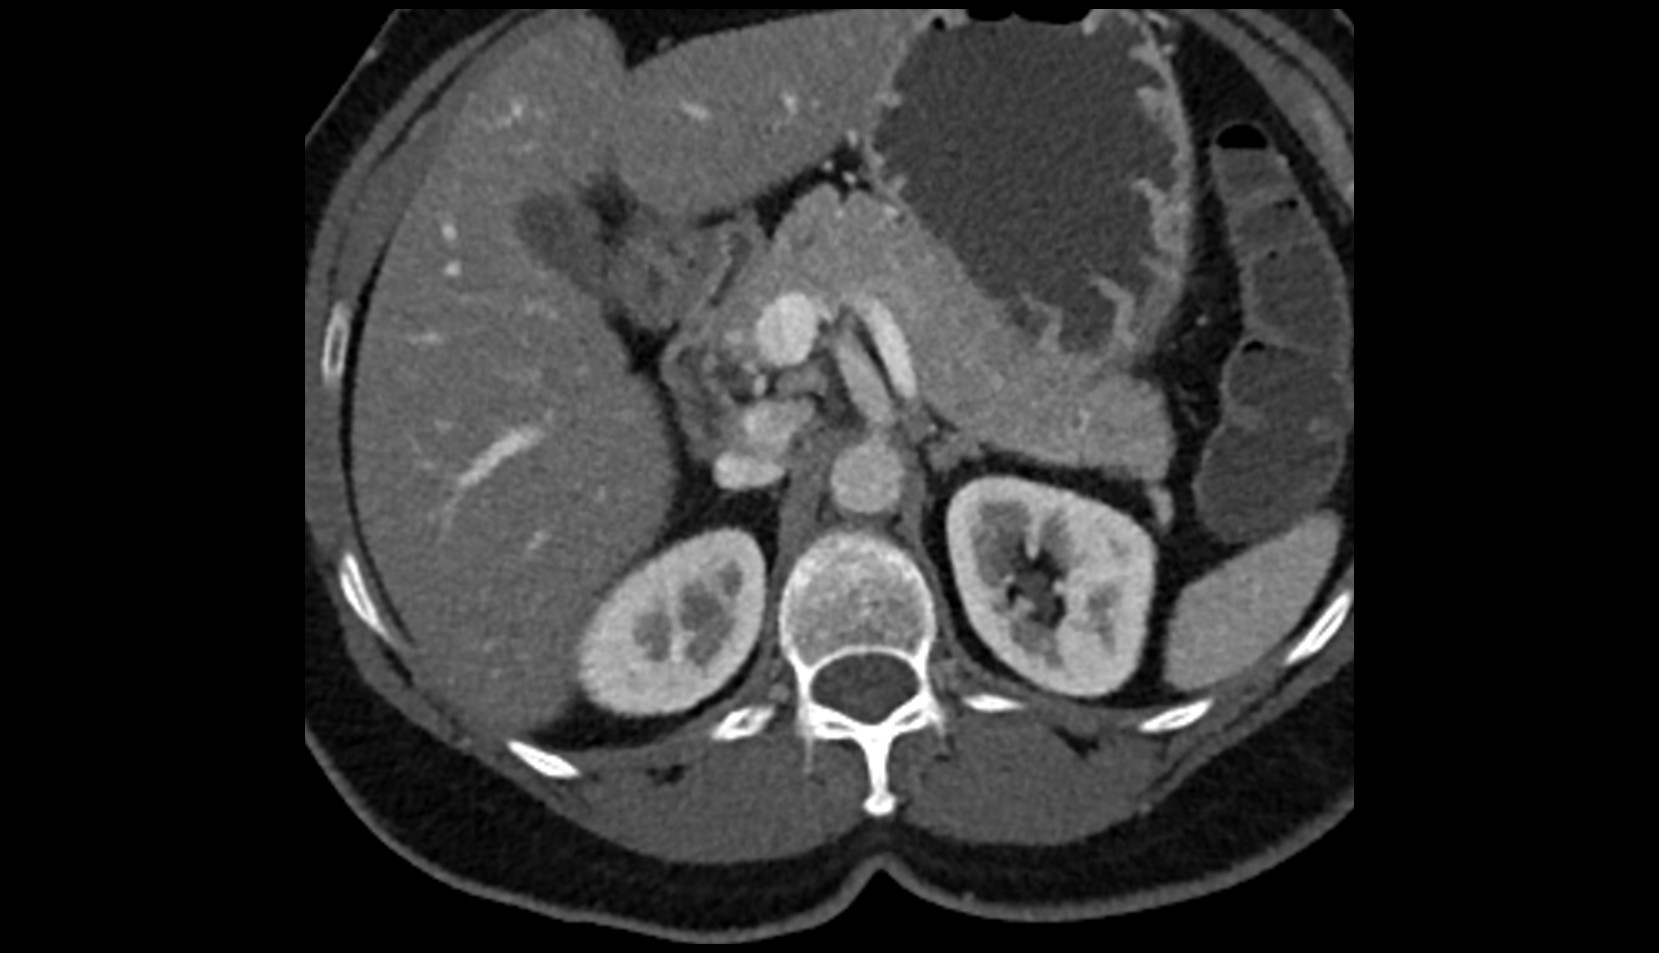

- kidneys

- Right kidney

- Left kidney

- Kidney cortex (Renal cortex)

- Renal capsule

- Renal medulla

- Renal pyramids

- Renal fascia

- Renal artery

- Renal vein